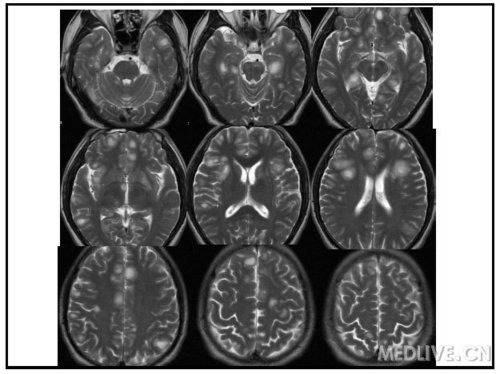

男性,31岁,头痛1月,反应迟钝、精神异常半月入院。